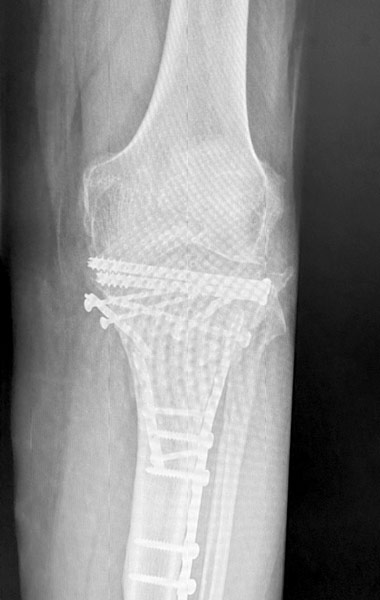

Homme 60 ans, Fracture complexe des 2 plateaux tibiaux opérée par plaques il y a 3 ans. Non consolidation osseuse.

Douleur, raideur.

Reprise par prothèse totale du genou postéro-stabilisée avec tige de reconstruction tibiale et reconstruction de l’appareil extenseur.